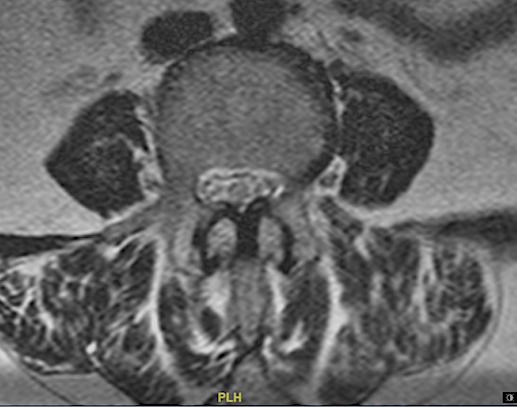

A continuación expongo imágenes de un caso prototipo donde podría estar indicado como alternativa a una descompresión y fusión larga.